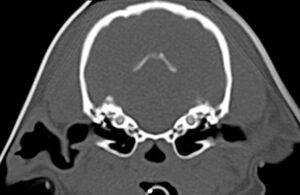

CTは骨構造を詳細に見ることができるが、脳や内耳は骨構造に囲まれているため、内部の構造の評価は困難。

脳や内耳の評価にはMRI検査が推奨される。